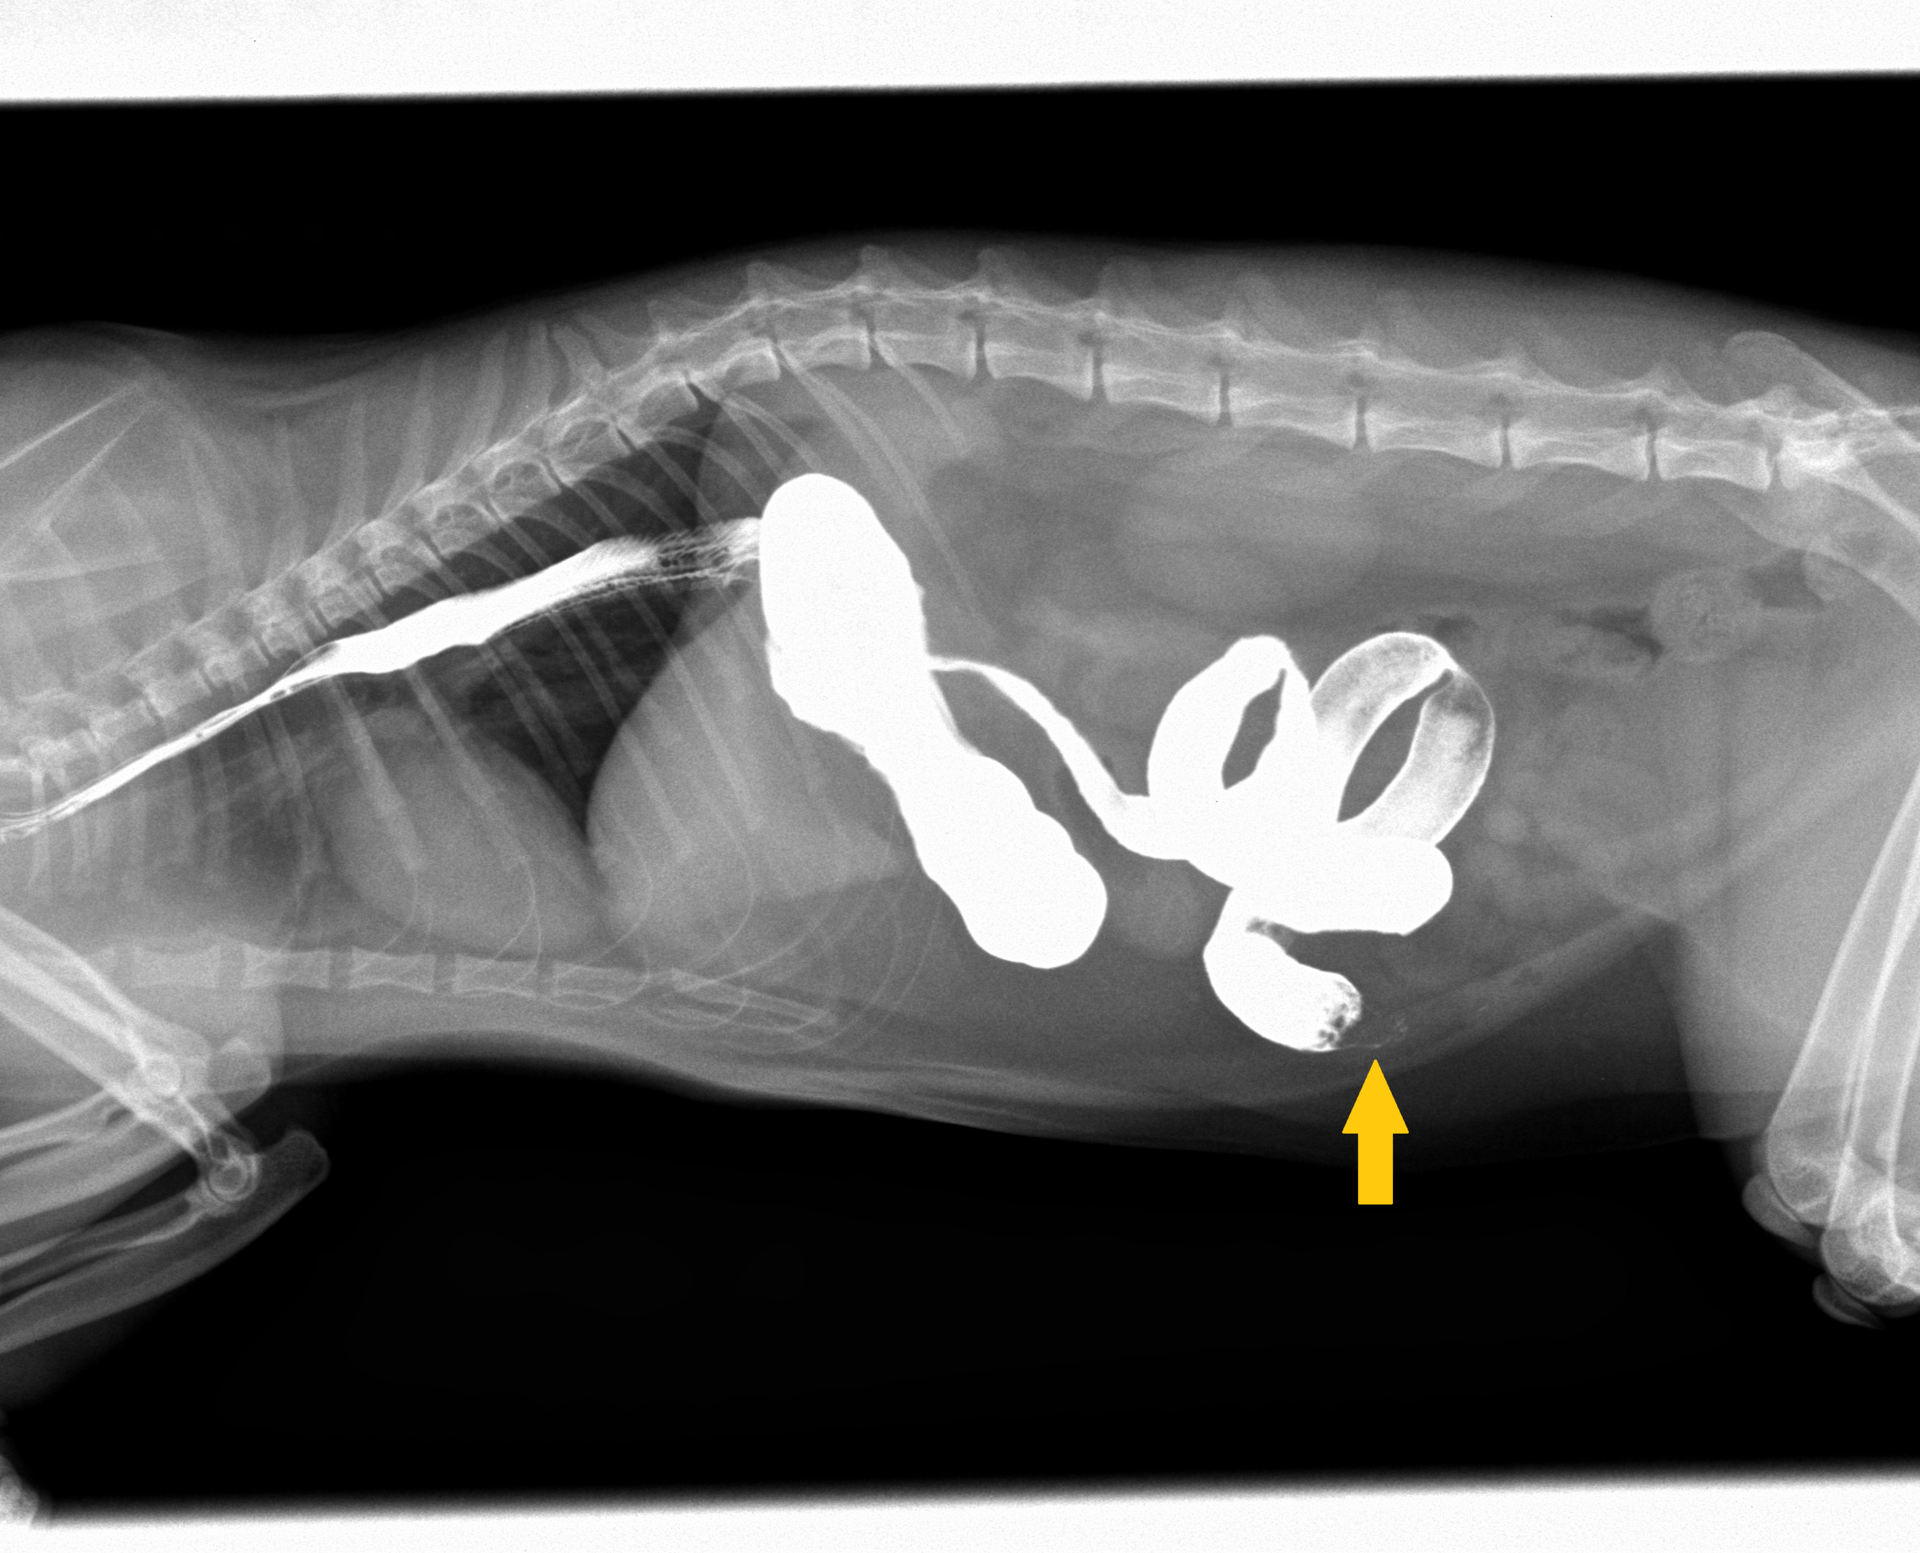

診察初日は点滴をし、その当日の絶食絶水を指示し、その日は自宅で様子を見ていただきました。しかしその次の日、嘔吐は治まらず吐き続けているということで来られました。そこで、異物がないかバリウム検査を行いました。その結果が下の写真です。

投与15分後

バリウムを投与後、15分も60分も同じところ(矢印)でストップして全く流れていないことがわかります。異物による通過障害が考えられたので、当日緊急手術となりました。その様子が下の写真です。